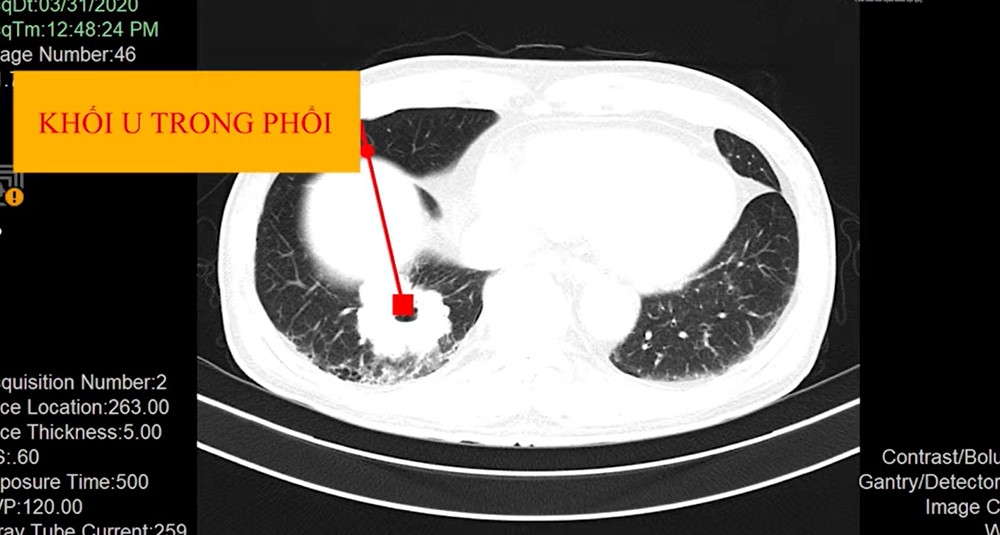

Với các cơ quan thiếu không khí như phổi, vai trò cộng hưởng từ không thể thay thế CT. Nói cách khác, CT có ưu thế trong việc chụp và khảo sát các khối u trong phổi. Ví dụ về một bệnh nhân nam lớn tuổi có tiền căn hút thuốc đi đến khám tại Bệnh viện Đa khoa Quốc tế S.I.S Cần Thơ, bác sĩ nghi ngờ bệnh nhân có bệnh lý về ung thư phổi. Nguyên nhân do thỉnh thoảng bệnh nhân có cơn ho kéo dài, không rõ nguyên nhân và đau nhói sau ngực.

Với hình ảnh chụp X-quang thông thường chỉ có thể nhận ra một vài dấu hiệu nghi ngờ. Thậm chí, hình ảnh X-quang phổi là bình thường nhưng bệnh cảnh lâm sàng bất thường như ho kéo dài, đau ngực kéo dài, hút thuốc. Tổ chức Y tế Thế giới khuyến cáo những bệnh nhân có tình trạng như vậy cần được tầm soát phổi. Vì vậy, khi chụp CT phổi cho bệnh nhân phát hiện có khối u trong phổi. Một trường hợp khác, bệnh nhân được đi khám bệnh nhiều nơi và chụp X-quang phổi nhưng không phát hiện tổn thương. Cho đến khi bệnh nhân có những tổn thương như đau ngực, sụt ký. Khi chụp CT mới phát hiện đó là ung thư phổi. Bên cạnh đó, CT có thể cho chúng ta biết bệnh nhân có bị chấn thương sọ não hay không. Khi bệnh nhân chấn thương sọ não, chúng ta sẽ sử dụng CT để đưa ra kết quả nhanh chóng. Chúng ta cũng có thể chụp CT động mạch vành để chẩn đoán bệnh động mạch vành. Nhưng chụp động mạch vành yêu cầu bơm thuốc cản quang.